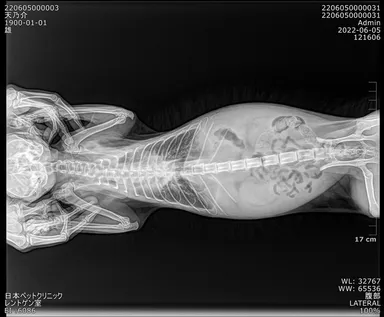

検査を重ねる中で、胸水は心臓のすぐ近くにまで来ていて危ない状態だということで、すぐにFIP治療を行うために入院をすることにもなりました。

現在は、週に1回、近くの病院での血液検査とレントゲン検査を行い、月に1回、大きな病院での血液検査とレントゲン検査を行っています。